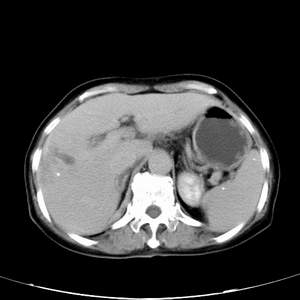

患者,女性,77岁,右上腹胀痛月余。afp正常。ca125升高。即往无肝炎病史。

肝右叶病灶是胆管细胞癌吗?门静脉右支癌栓形成?右侧肾上腺有问题吗?

最后5幅图片是延时7分钟的。门静脉右前支内有充缺吗?如有,肝血管瘤不好解释。

病灶渐进性向心性强化,延时病灶中心见条片状高密度影,局部见肝包膜回缩征,结合病人无肝炎病史,考虑肝右叶胆管细胞癌,门脉右支癌栓形成。